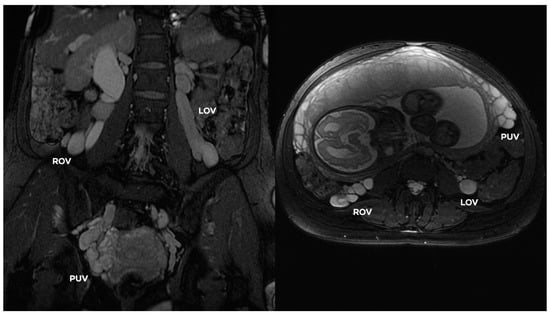

4.2. Grading of Ovarian Veins Insufficiency

| øLOV | incLOV | lPUV | bLIILV | øROV | incROV | rPUV | bRIILV | |

|---|---|---|---|---|---|---|---|---|

| GI | <6 | (−/+) | <5 | <5 | <5 | (−) | <5 | <5 |

| GI/II | 6–6.5 | (+) | <5.5 | <5.5 | <5 | (−) | <5 | <5 |

| GII | <7 | (+) | <6.5 | <6 | <5.5 | (−) | <5.5 | <5.5 |

| GII/III | 7.5–8 | (++) | <7 | <7 | <6 | (−/+) | <6.5 | <6 |

| GIII | >8 | (++) | 7–8 | <7.5 | <7.5 | (+/++) | <7 | <6.5 |

| GIV | >10 | (+++) | >8 | >8 | >8 | (+++) | >7.5 | >7 |